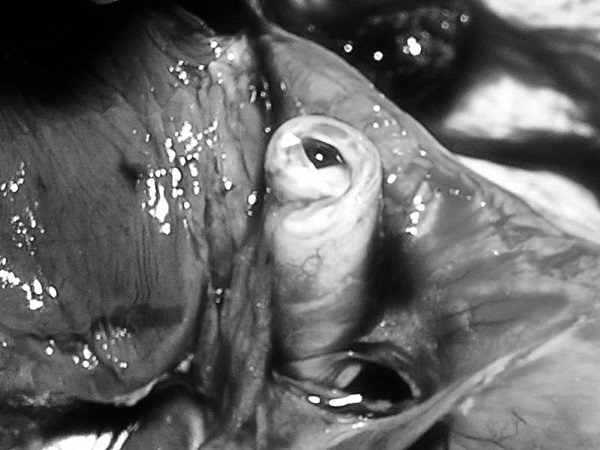

В посмертном эпикризе указан Основной диагноз: последствия ОНМК от 2008 года. ИБС. СН 2. ПИКС. Фоновое: СД 2-го типа, сопутствующее: хронический пиелонефрит. Осложнения: внебольничная пневмония. На секции: ![]() Рис. 31. Последствия перенесенного ОНМК ![]() Рис. 32. Атеросклероз церебральных артерий ![]() Рис. 33. Постинфарктный кардиосклероз ![]() Рис. 34. Гипертрофия миокарда левого желудочка ![]() Рис. 35. Признаки ХСН: мускатный фиброз печени ![]() Рис. 36. Пневмония ![]() Рис. 37. Признаки хронического пиелонефрита Анализируя данный клинический пример, необходимо отметить следующее. 1. Социальный статус. Социальный статус, за исключением указания на участие в ВОВ, не обозначен. 2. Наблюдение на дому. Полное несоблюдение регламента наблюдения ДИП. Клинический диагноз. Записи в амбулаторной карте нет. При этом диагноз должен быть следующим. Основной: последствия ОНМК от 2008 года. ИБС. Постинфарктный кардиосклероз. Фоновое: гипертоническая болезнь 3-й ст., 3 ст. риск 4. СД 2-го типа. Осложнения: длительная иммобилизация. Внебольничная пневмония. НК 2. Хронический пиелонефрит. Анемия. 3. Обоснованность назначения лекарственных препаратов. Терапия СД проводилась вне соответствия с клиническими рекомендациями, контроль за уровнем гликемии не осуществлялся, лечение анемии отсутствовало, вместе с тем при отсутствии подтвержденных данных за пиелонефрит были назначены антибиотики. Таким образом, наряду с указанными замечаниями врач не оценил тяжесть состояния, что не позволило решить вопрос о показанной госпитализации. Приложение № 6 – алгоритм лечения анемии. Приложение № 7 – самоконтроль уровня глюкозы. Пациентка Ф., 84 года. Умерла в январе 2011 года. Иммобилизирована с марта 2010 года в связи с закрытым переломом лонной и седалищной костей. В карте ежемесячные осмотры терапевта в связи с активами СМП. Причина вызовов: гипертонические кризы и болевой синдром. За год до смерти проведены доступные на дому анализы. В плановом порядке в апреле 2010 году проходила стационарное лечение в терапевтическом отделении. Диагноз при выписке: дисциркуляторная энцефалопатия 2-й ст. ГБ. ИБС. СН 3. ПИКС от 2001 года. Железодефицитная анемия. Закрытый перелом лонной и седалищной костей справа. Амбулаторно после стационара принимала энап Н и винпоцетин. В посмертном эпикризе указан Основной диагноз: 1) дисциркуляторная энцефалопатия 2-й ст. и ИБС. СН 3. ПИКС от 2001 г. НК 2А. Фоновое: ГБ. Сопутствующее: хроническая железодефицитная анемия. Закрытый перелом лонной и седалищной костей от 11.03.2010. ![]() Рис. 38. Повторный инфаркт головного мозга ![]() Рис. 39. Постинфарктный кардиосклероз ![]() Рис. 40. Атеросклероз коронарных артерий ![]() Рис. 41. Проявления НК: мускатный фиброз печени ![]() Рис. 42. Острые эрозии желудка ![]() Рис. 43. Атеросклероз аорты Замечания к ведению больного следующие: 1. Социальный статус. Информации нет. 2. Наблюдение на дому. Посещение терапевта осуществлялось только в связи с активами СМП. 3. Клинический диагноз. Нет правильной формулировки диагноза. При этом правильный диагноз был бы следующим. Основной диагноз: 1) Повторный инфаркт головного мозга. 2) ИБС. Постинфарктный кардиосклероз от 2001 года. Фоновое: гипертоническая болезнь 3 ст., 3 ст. Осложнения: закрытый перелом лонной и седалищной костей от 11.03.2010. Длительная иммобилизация. НК 2. Острые эрозии. Хроническая железодефицитная анемия. Сопутствующие: атеросклероз аорты. 4. Обоснованность назначения лекарственных препаратов: лекарственная монотерапия ГБ эналаприлом неэффективна, что повлекло за собой неоднократные гипертонические кризы и вызовы СМП, нет лечения проявлений ПИКС и анемии. Таким образом, не было оценки тяжести состояния, наличия тяжелой степени АГ у больной с перенесенным ОНМК и инфаркта миокарда, кризовым течением и признаками СН, что требовало госпитализации пациента. Приложение № 8 – ведение больного, перенесшего инфаркт миокарда. Пациентка Б., 95 лет. Иммобилизирована. Карта малоинформативна. Осмотры терапевта 1–2 раза в год, лист впервые выявленных диагнозов не ведется. Анализы отсутствуют. Известно, что наблюдалась с диагнозом ИБС, ЦВБ. Хронический бронхит. ОНМК с левосторонним гемипарезом и перелом шейки бедра без указания давности. В карте имеются указания на пролежни. За последние 2 года до смерти терапевтом были назначены: пирацетам, предуктал, мексидол, проведен курс ЛФК на дому. Посмертный эпикриз отсутствует. На секции: ![]() Рис. 44. Последствия перенесенного инфаркта головного мозга ![]() Рис. 45. Постинфарктный кардиосклероз |